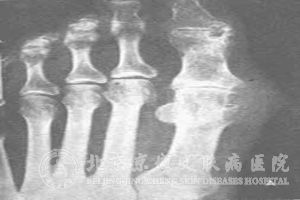

痛风的常见护理问题有哪些呢?痛风在我国的发病率在逐年上升,而且在治疗上存在着很多的问题。由于痛风会对患者的身体造成损害,所以痛风给患者的生活造成了不可忽视的影响。由于人们对于痛风的认识浅薄,所以对于痛风的护理也不清楚。那么痛风的常见护理问题有哪些呢?

1、 关节疼痛;